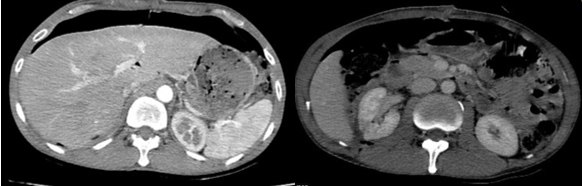

- CTscanner ổ bụng: Phát triển từ khoang sau phúc mạc bên phải có khối lớn kích thước khoảng 253x127mm, tỷ trọng hỗn hợp gồm phần đặc ngấm thuốc sau tiêm, thành phần nang dịch, mỡ và các ổ tăng tỷ trọng tự nhiên trước tiêm dạng máu cục lớn nhất kích thước khoảng 83x64 mm theo dõi liposarcoma. Khối lớn đẩy thận phải ra trước, sang trái sát đường giữa, đẩy nhu mô gan lên trên và đẩy các quai ruột trong ổ bụng sang trái. Không ghi nhận tổn thương ở các cơ quan khác.

Hình 2. Hình ảnh chụp cắt lớp vi tính ổ bụng: Khối khoang sau phúc mạc – Theo dõi Liposarcoma (vòng tròn màu đỏ)